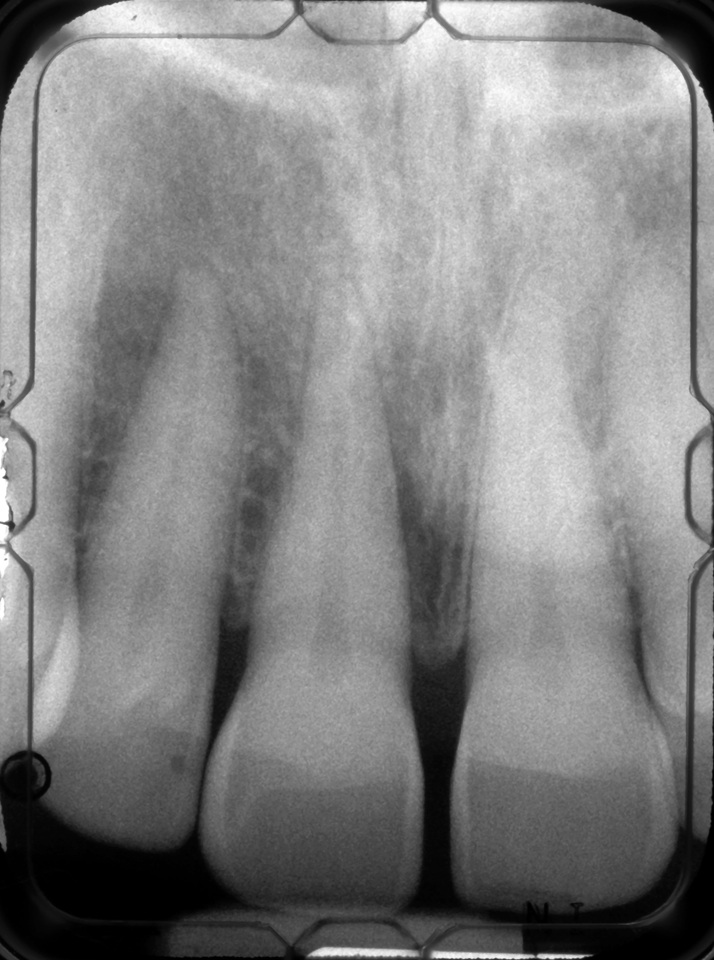

The 9-year postoperative radiograph.

Fig. 7

Then, too, are opportunities to prepare the site for regeneration by coupling therapies, applying an enamel matrix derivative, along with traditional bone grafts of demineralized freeze-dried bone allograft; potentially, gains in attachment with minimal probing depth and retained papilla may avoid the need for an implant (Figure 2 through Figure 7).